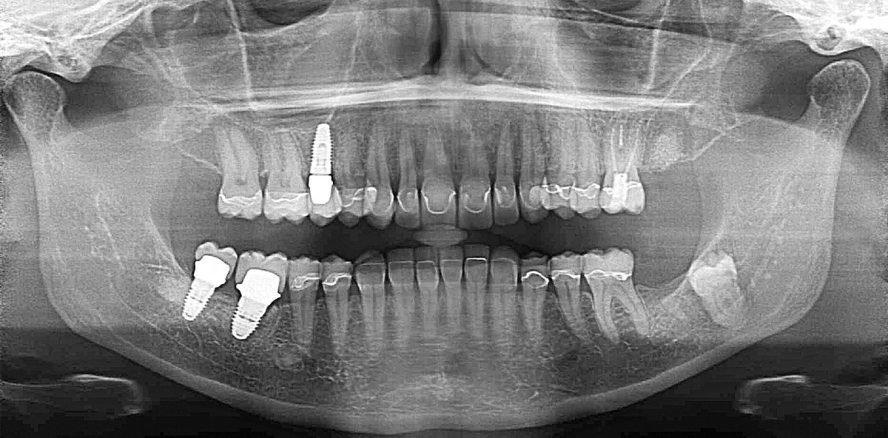

OPG

Das OPG (Abb. 7) gibt keinen Anhalt auf nicht zahnverursachte Prozesse – retinierter Zahn 38, Elongation 27. Insuffiziente Amalgam- und Kompositfüllungen vor allem im Seitenzahn­bereich des Ober- und Unterkiefers. Des Weiteren sind insuffiziente Wurzel­füllungen an 15 und 46 feststellbar und die UK-Frontzähne stehen in einer ­Supraposition.